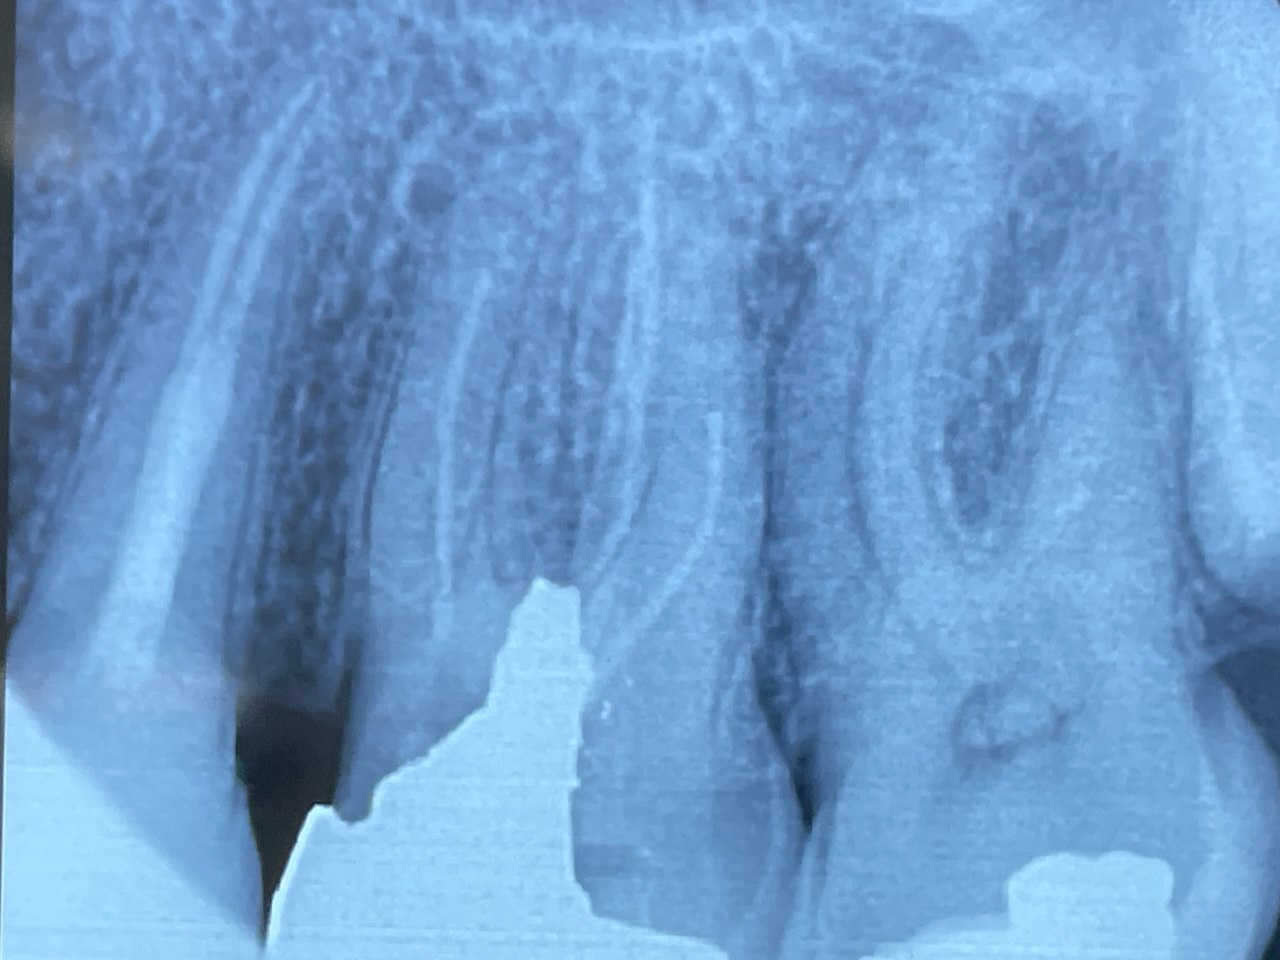

7. What condition can be selected or the root canal treatment of tooth # 4.6?

8. What condition can be selected or the root canal treatment of tooth # 3.6?